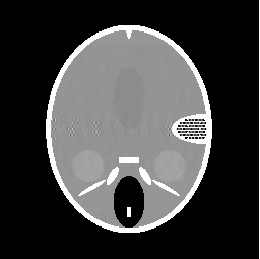

In this section we report the results of several tests run on simulated under-sampled data obtained by synthetic (phantoms) and full resolution MRI images. The under-sampled data are obtained as where is the full resolution image and is the under-sampling Fourier matrix, obtained as in (5). The under-sampling masks, analyzed in the next paragraphs are: radial mask (), parallel mask () and random mask (). In figure 1 we represent an example of each mask with low sampling rate , measured by the percentage ratio between the number of non-zero pixels and the total number of pixels :

| (48) |

In this paragraph we test the performance of FNCR algorithm in reconstructing good quality images from highly under-sampled data. We focus on two synthetic images: the Shepp-Logan phantom (T1) (figure 2(a)), widely used in algorithm testing, and the Forbild phantom (T2) [21] (figure 2(b)), well known as a very difficult test problem.

Concerning the real MRI data we compare IL and FNCR algorithms in the reconstructions of the brain image (T3 test), represented in figure 8. We report in table 6 the results obtained by reconstructing the noiseless data undersampled by , , masks.